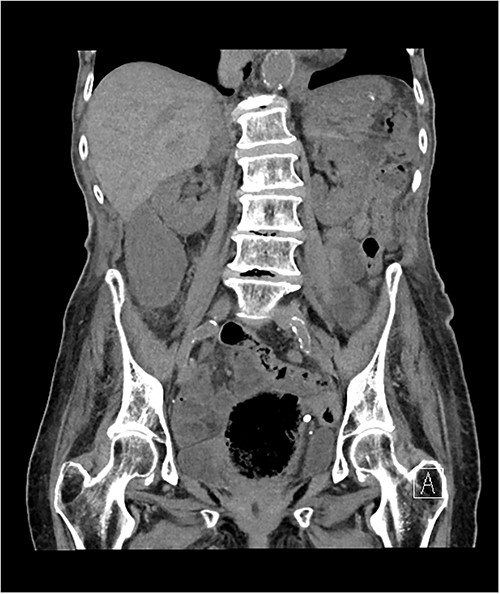

The morning after her admission, she began to complain of right-sided abdominal pain that coincided with a rise in her inflammatory markers. She proceeded for a non-contrast computed tomography (CT) of her abdomen and pelvis due to her poor renal function. The CT scan demonstrated a very distended gallbladder causing medial displacement of the right kidney and hepatic flexure of the ascending colon (Fig. 1). The gallbladder was inferior to the right liver lobe rather than the typical anatomical position within the gallbladder fossa and was suspicious for gallbladder volvuli.

Axial slice of non-contrast CT abdomen and pelvis, demonstrating a distended gallbladder located outside the typical anatomical location, inferior the liver edge, causing medial displacement of the right kidney.